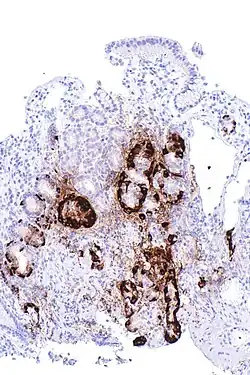

| Micrograph showing nodular enterochromaffin-like cell hyperplasia, as demonstrated with chromogranin A immunostaining, in the body of the stomach. Parietal cells are not readily apparent. These changes are in keeping with autoimmune metaplastic atrophic gastritis, a histologic correlate of vitamin B12 deficiency anemia. | |

PA may be considered as an end stage of autoimmune atrophic gastritis, a disease characterised by stomach atrophy and the presence of antibodies to parietal cells and intrinsic factor.[38][39] Autoimmune atrophic gastritis, is localised to the body of the stomach, where parietal cells are located.[36] Antibodies to intrinsic factor and parietal cells cause the destruction of the oxyntic gastric mucosa, in which the parietal cells are located, leading to the subsequent loss of intrinsic factor synthesis. Without intrinsic factor, the ileum can no longer absorb the B12.[40] Atrophic gastritis is often a precursor to gastric cancer.[39]